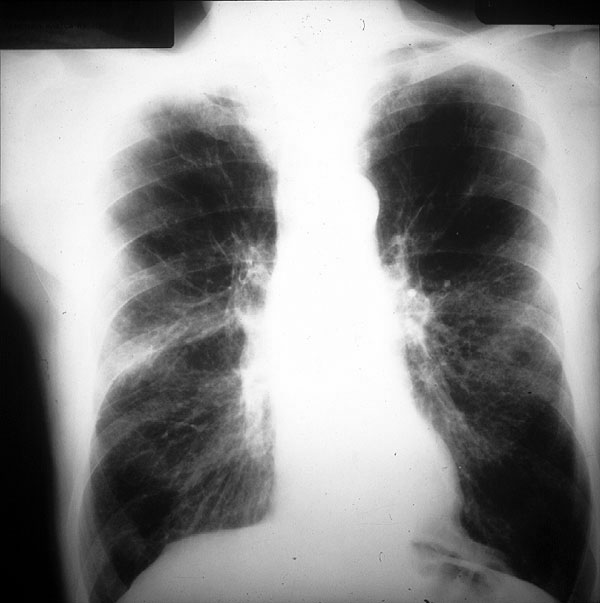

Placa 36